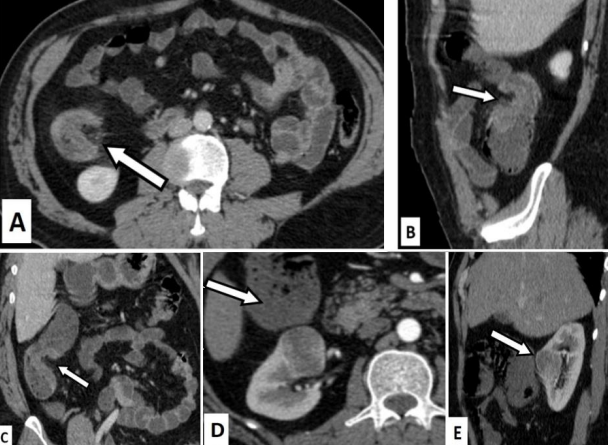

Figure 2: True positive for T3 and N positive disease.

A 65 years old female presented with PR bleed. Ultrasound done showed dilated small and large bowel loops.

Figures 2A (axial), 2B (coronal) and 2C (Sagittal) CT images in venous phase show telescoping of sigmoid colon into the rectum suggestive of intussusception (arrows). The pericolic fat appears normal, however an enhancing mass can be seen at the of the intussusception. Multiple sub centimetric lymph nodes are seen (arrowheads).

Figure 2D (magnified axial CT image in venous phase) shows cluster of nodes with perinodal stranding. One of the nodes shows heterogeneous enhancement (arrowhead).

T3, N positive disease was confirmed on post-operative histopathology.

Figure 5: Example of true positive for T2 and N0 stage of the tumor.

48 years old male presented with complaints of altered bowel habits. He underwent colonoscopy which showed ulcero-proliferative caecal growth and subsequently mucosal biopsy was obtained. Histopathology showed moderately differentiated mucinous adenocarcinoma. CT was don pre operatively for staging.

Figures 5A (axial CT image), 5B(sagittal CT image) and 5C (coronal CT image) show asymmetric eccentric enhancing wall thickening involving the caecum and ascending colon (arrows) without any significant pericolic stranding. No significant nodal involvement can be seen. Figures 5D (axial arterial phase image) and E (sagittal venous phase image) show a well-defined hyper enhancing lesion in the mid pole of right kidney.

The patient underwent right hemicolectomy with partial right nephrectomy. Postoperative histopathology confirmed the presence of T2 N0 disease. The renal lesion was diagnosed as a renal oncocytoma.